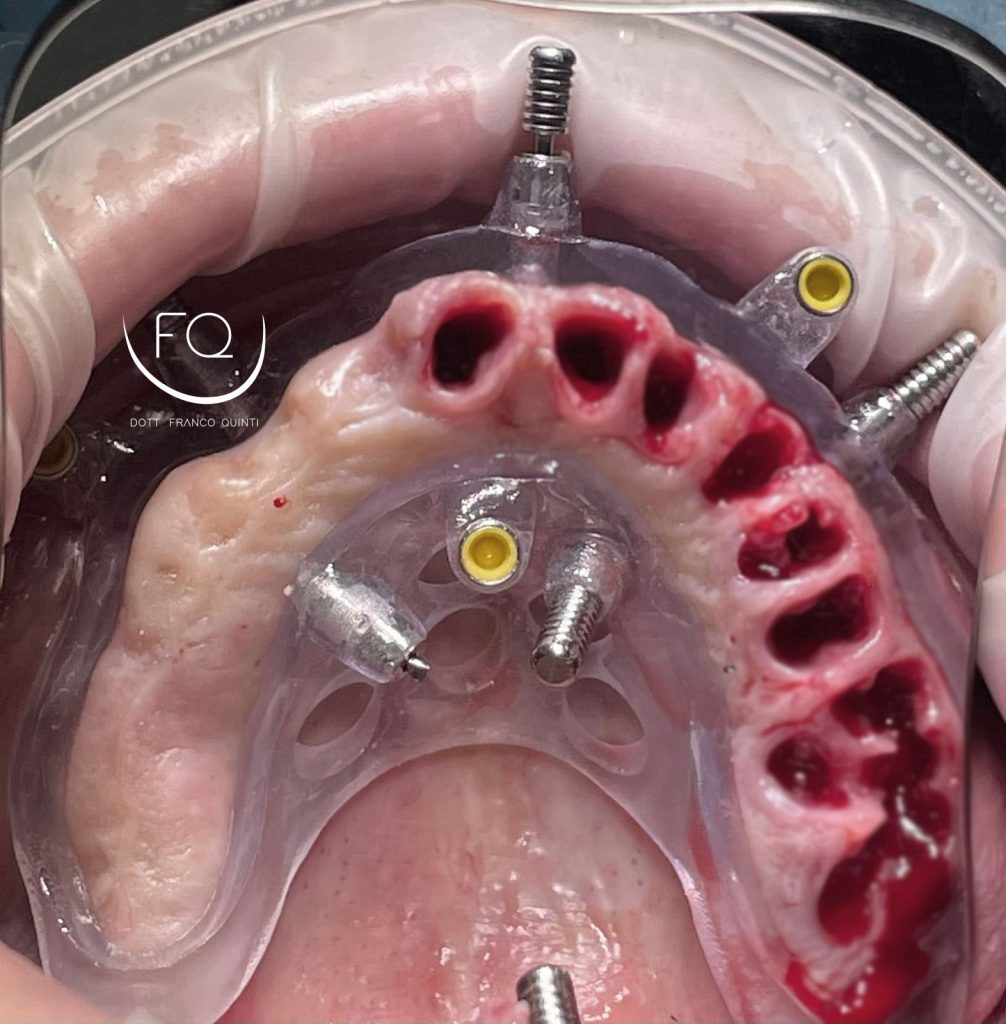

Questa settimana vi presento un caso di chirurgia computer guidata dell’arcata superiore realizzato con dime scomponibili con esecuzione contestuale di un carico immediato.

Nelle prossime settimane vi mostrerò dei brevi video di questo caso relativi alla scomposizione e alla progettazione delle dime chirurgiche.